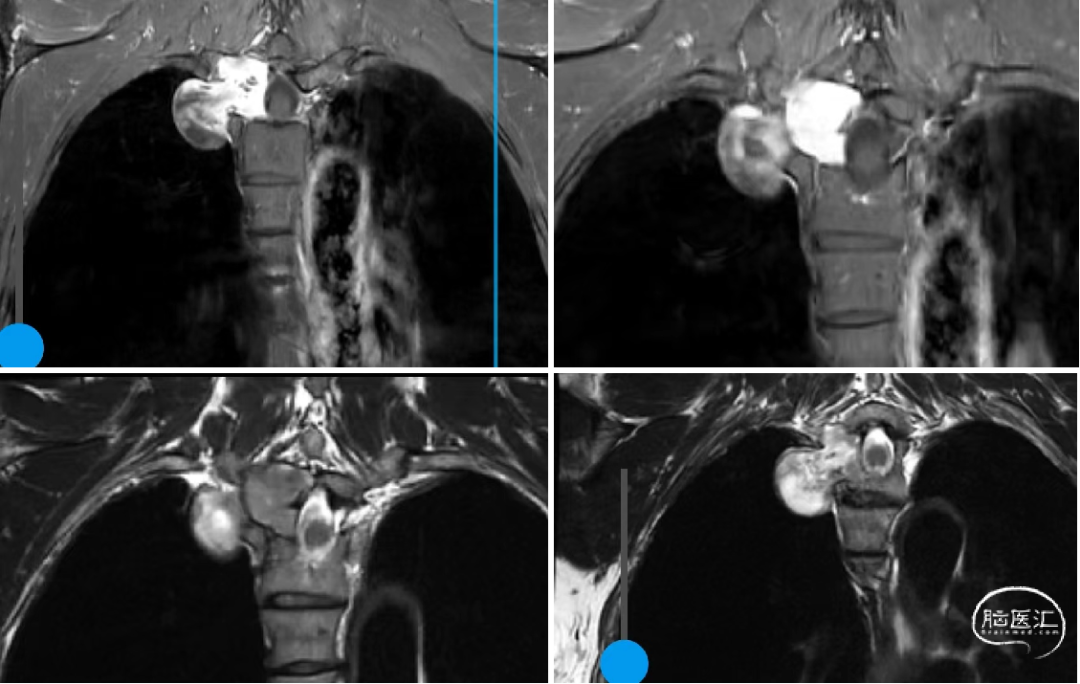

辅助检查:胸椎CT和MR示:T3/4右侧椎间孔扩大,见一类圆形低密度灶,大小约45mm×31mm,边界较清,信号不均,部分突入椎管内,右侧椎弓根骨质受压,见骨质吸收,考虑神经源性可能性大等。

术前胸椎MR如下:

T3/4右侧椎旁哑铃型肿瘤:神经鞘瘤?